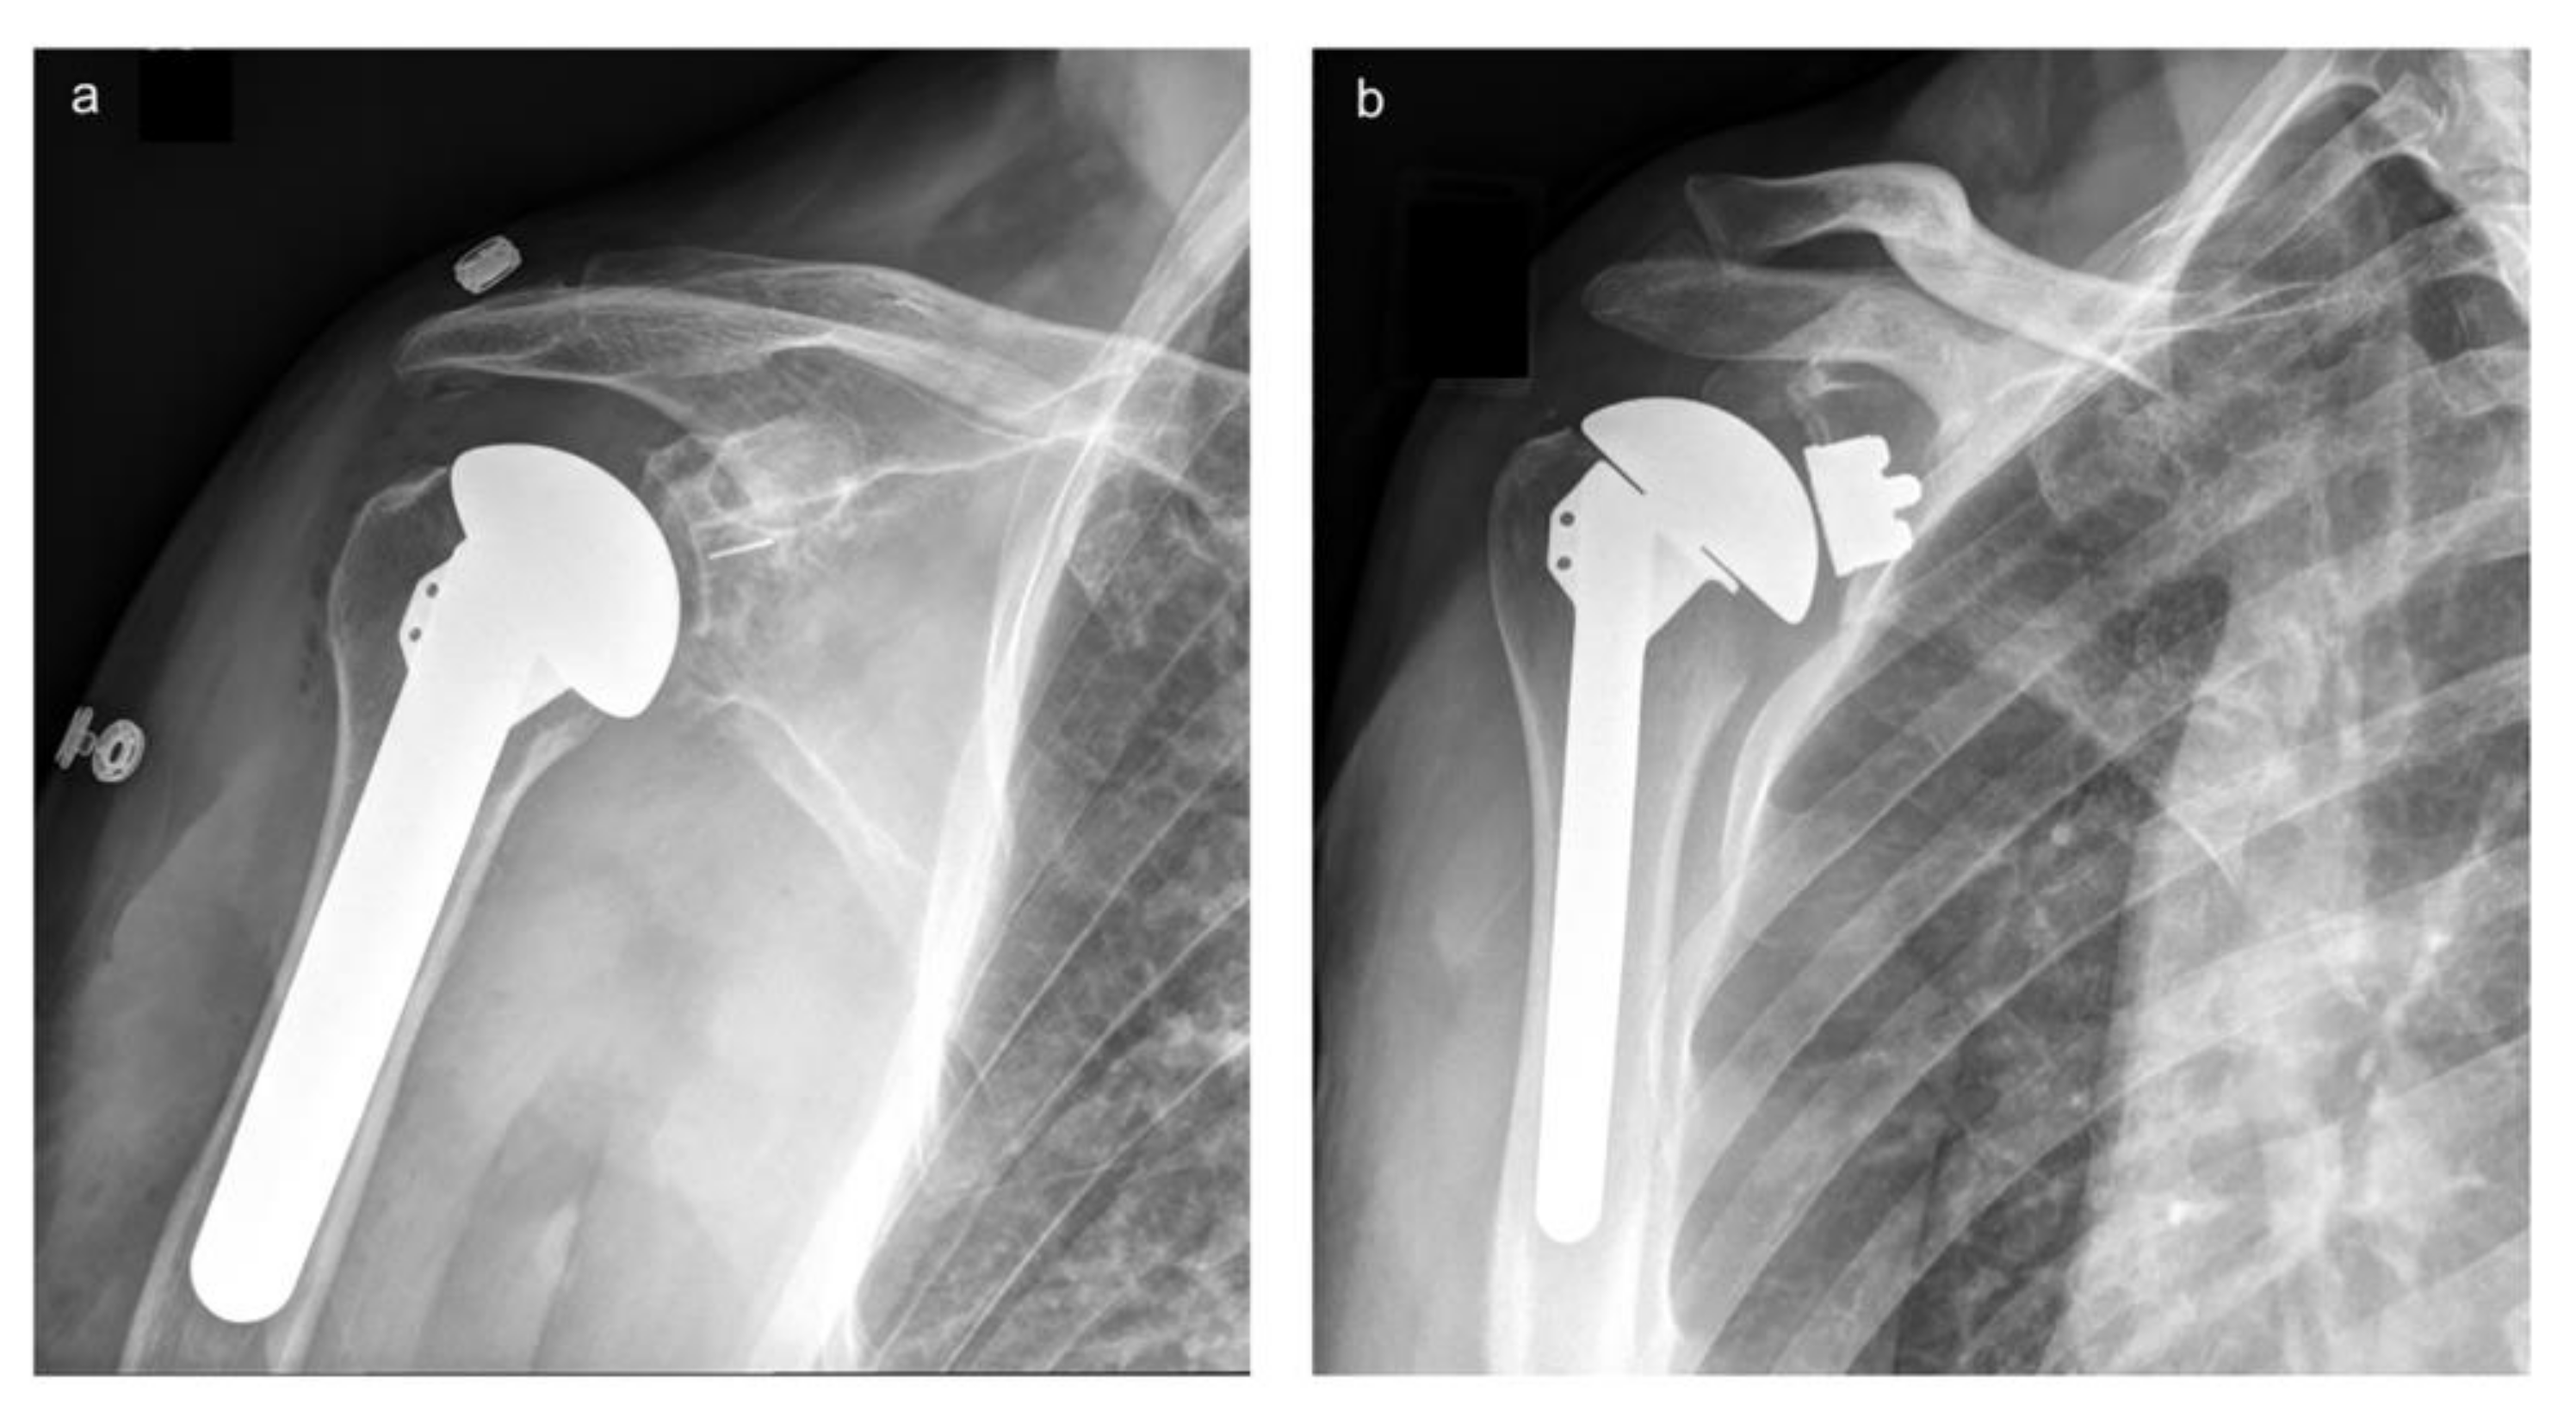

2.2. Radiographic Measures